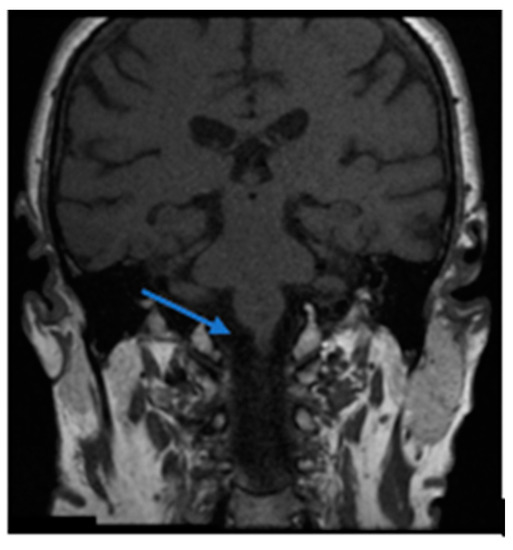

Cohort A (OC) included 16 patients, 62.5% female, with a mean age of 70.5 years (SD 12.65), and an average of 79.7 days between symptom onset and first evaluation. 31.3% of the patients in this cohort had a prior history of BPPV, affecting the posterior semicircular canal in all cases. In one patient of this subgroup, there was a combination of pc-BPPV and hc-BPPV-cu. 43.8% of patients in the Cohort A had multicanal BPPV (mc-BPPV) at the time of hc-BPPV-cu diagnosis, involving a combination of posterior canal and horizontal canal. In 62.5% of cases, hc-BPPV-cu resolved with a single maneuver (the first particle displacement maneuver performed after diagnosis), with the Gufoni maneuver being the most used (37.5%). In contrast, 25.1% of the patients required more than one treatment maneuver for resolution, with 25% of them requiring a change of maneuver, and in 2 patients (12.5%) the hc-BPPV-cu persisted for the duration of follow-up, both of whom had a central cause identified on further brain imaging, shown later (Figure 1).

Figure 1.

Right hemipontine ischemia (blue arrow). This patient associated cardiovascular risk factors (arterial hypertension and dyslipidemia) together with right-sided hearing loss and unsteadiness.

Notably, hc-BPPV-cu was not resolved in 2 patients attending the OC and in 3 from the ED. All of these showed central pathology on subsequent MRI brain scans, thus mimicking hc-BPPV-cu, but presented with additional neurological symptoms. In the OC cohort, one patient with a hemipontine stroke (Figure 1) had associated cardiovascular risk factors (arterial hypertension and dyslipidemia) together with right-sided hearing loss and marked unsteadiness. The second patient with cerebellar atrophy, associated instability and a cerebellar pattern videonystagmogram and a left vestibular deficit of 28%. In the ED cohort, one patient had a stroke due to bilateral Posterior Inferior Cerebellar Artery (PICA), associated with cardiovascular risk factors (arterial hypertension, atherosclerosis and diabetes mellitus), unsteadiness and gait ataxia; another patient had dissection of the vertebral artery, associated with severe neck pain; the third patient was found to have metastasis in the cerebellar hemisphere, in the context of a personal history of metastatic colon cancer, headache and profuse positional vomiting (Figure 2).

A comprehensive approach to the dizzy patient remains critical even in the setting of an Outpatient Clinic (rather than an acute setting), where careful symptom evolution should be monitored, particularly where the natural history is atypical for that condition (e.g., lack of resolution of nystagmus despite appropriately conducted maneuvers for BPPV [23]). This lack of resolution of hc-BPPV-cu alerted us to diagnose central pathology in all our patients in cohort A. Furthermore, as in the case of the patient with a right hemipontine stroke, the presence of cardiovascular risk factors (arterial hypertension and dyslipidemia) [30], together with otological symptoms atypical for BPPV (hearing loss) should be taken into consideration, even in the presence of positional nystagmus typical for BPPV. Positional nystagmus in hemipontine stroke may be explained by nystagmus mechanisms similar to those in inferior cerebellar peduncle lesions, due to its close anatomical association. The inferior cerebellar peduncle contains cerebellar afferents, including the dorsal spinocerebellar tract and the axons from the vestibular nuclear complex and inferior olivary nucleus. Thus, lesions in these areas affect the integration of proprioceptive, sensory and vestibular signals. This triggers an apogeotropic nystagmus beating to the lesion side (ipsilesional nystagmus) [34]. The patient with cerebellar atrophy was diagnosed in OC, too. This patient showed marked gait ataxia. Concerning this pathology, attempts have already been made to correlate cerebellar atrophy with BPPV, although conclusive results have not been previously obtained [35].